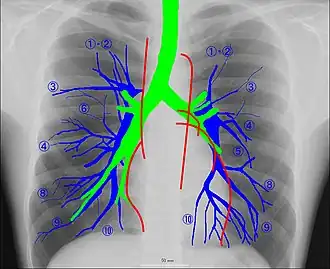

Рентгеноанатомия органов грудной клетки.

Рентгеноанатомия органов грудной клетки. Зелёным обозначены трахея и крупные бронхи, синим — ветви лёгочных артерий, красным — дуги тени сердца, цифрами отмечены сегменты лёгких.

При изучении рентгеноанатомии органов грудной клетки обращают внимание на рентгеновскую структуру видимых костей и мягких тканей грудной клетки; форму и прозрачность для рентгеновских лучей областей, на которые проецируется лёгочная ткань (так называемых «лёгочных полей»), а также их структуру, сформированную тенями сосудов лёгких («лёгочный рисунок»); расположение и структурность корней лёгких; положение, форму куполов диафрагмы и синусов плевральных полостей; форму и размеры тени средостения (в том числе сердца).

Лёгкие на рентгенограмме образуют лёгочные поля, располагающиеся по обе стороны от интенсивной тени средостения. Правое лёгочное поле короче и шире левого. В лёгочных полях различают верхушки (зоны выше ключиц), верхние отделы — от верхушек до передних отрезков вторых рёбер, средние отделы — между вторыми и четвёртыми парами рёбер, и нижние отделы — от четвёртых рёбер до диафрагмы. Лёгочные поля в норме очень светлые (тёмные на негативе) из-за высокой рентгенопроницаемости заполненной воздухом лёгочной ткани. Структура лёгочных полей называется лёгочным рисунком, анатомическим субстратом которого являются лёгочные сосуды и, в малой степени, лёгочный интерстиций. Лёгочный рисунок визуализируется в виде переплетения сосудистых теней тяжистого, округлого и овального вида, более интенсивных в местах их пересечений. В направлении от корней лёгких к периферии рисунок лёгочных сосудов становится беднее и совсем не визуализируется на расстоянии 1—1,5 см от края лёгочных полей. Лёгочный рисунок наиболее густой в нижних отделах лёгочных полей, обедняясь к верхушкам. Тени бронхов на рентгенограмме визуализируется в виде двойных полосок или колец с просветлением внутри.[3][4]

Корни лёгких.

Тень корней лёгких определяется парамедиастинально на уровне передних отрезков II—IV рёбер, левый корень располагается несколько выше правого и частично скрыт тенью средостения. Ведущим анатомическим субстратом в формировании тени корней лёгких являются лёгочные артерии и бронхи, в меньшей степени — лёгочные вены и другие структуры. В норме корни лёгких имеют неоднородное изображение, представляя собой структурированную совокупность элементов различной плотности. В корнях лёгких различают головку, тело и хвост. Правый корень визуализируется на всём протяжении в виде лентовидной, суживающейся книзу изогнутой тени средней интенсивности, отделённой от тени сердца промежуточным и нижнедолевым бронхами. К периферии от корней лёгких отходят лёгочные сосуды, причём артериальные ветви имеют более вертикальное направление, венозные — более горизонтальное. Ширина корня лёгкого соответствует ширине его основного артериального ствола; в норме она равна ширине бронха, отделяющего корень от средостения, и не превышает 1,5 см.[3][4]

Тень средостения.

Сердечно-сосудистая тень занимает центральное положение на рентгенограмме органов грудной клетки. На рентгенограмме в прямой проекции её контуры в норме формируют две дуги справа и четыре — слева. Нижняя дуга правого контура образована правым предсердием, верхняя, более медиальная — восходящей частью аорты и верхней полой веной. Первая (верхняя) левая дуга образована дугой и начальным отделом нисходящей аорты, вторая — лёгочным стволом, третья — ушком левого предсердия, четвёртая — левым желудочком. В области второй и третьей дуг контур тени средостения вогнут и носит на этом уровне название «талия сердца»; эта зона является границей между сердцем и связанными с ним сосудами.[5]